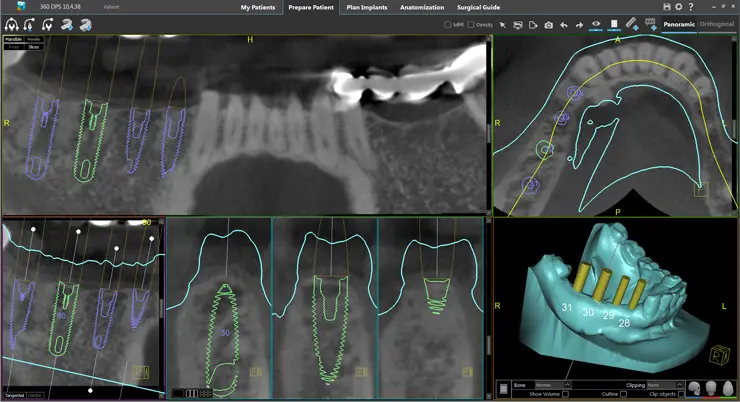

The no cost implant evaluation entails a no cost Panoramic X-ray and an examination to provide you with a treatment plan that is based on your individual needs. Your provider may request that a Cone Beam CT scan (3-dimensional dental scan) be obtained in order to further evaluate and finalize treatment planning. The fee for this scan is $200.00, which will be collected at the time the scan is taken. This scan is not typically covered by most insurance companies; however, we are happy to file a claim if requested, and you will be reimbursed if payment is rendered by your insurance.